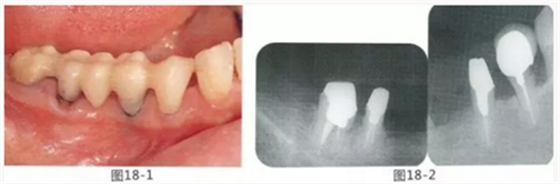

58歲女性,在修復治療前,為了去除牙周袋和獲得附著齦,頰側進行APF(齦瓣根尖側轉移),FGG(游離齦移植),舌側進行APF(齦瓣根尖側轉移)進行對應的病例

圖18-1 右上4,5,6,6,7部位,初期治療結束時牙齦的狀態(tài)。

圖18-2 手術前同部位的口腔X光片。